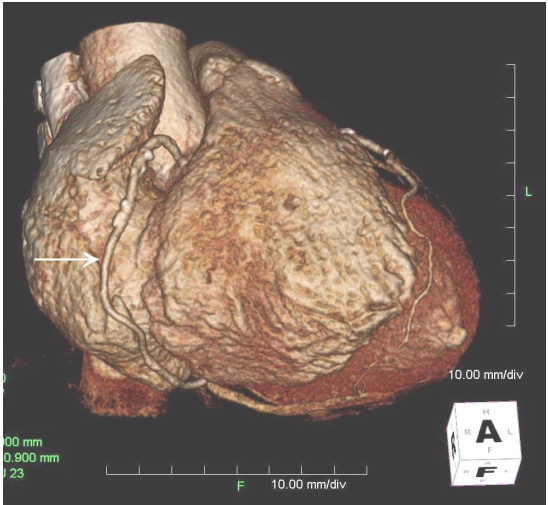

74 附圖心臟 CT 影像重組中箭頭所指為下列何者?

(A)冠狀靜脈竇(Coronary sinus) (B)左前降動脈 (C)左迴旋動脈 (D)右冠狀動脈